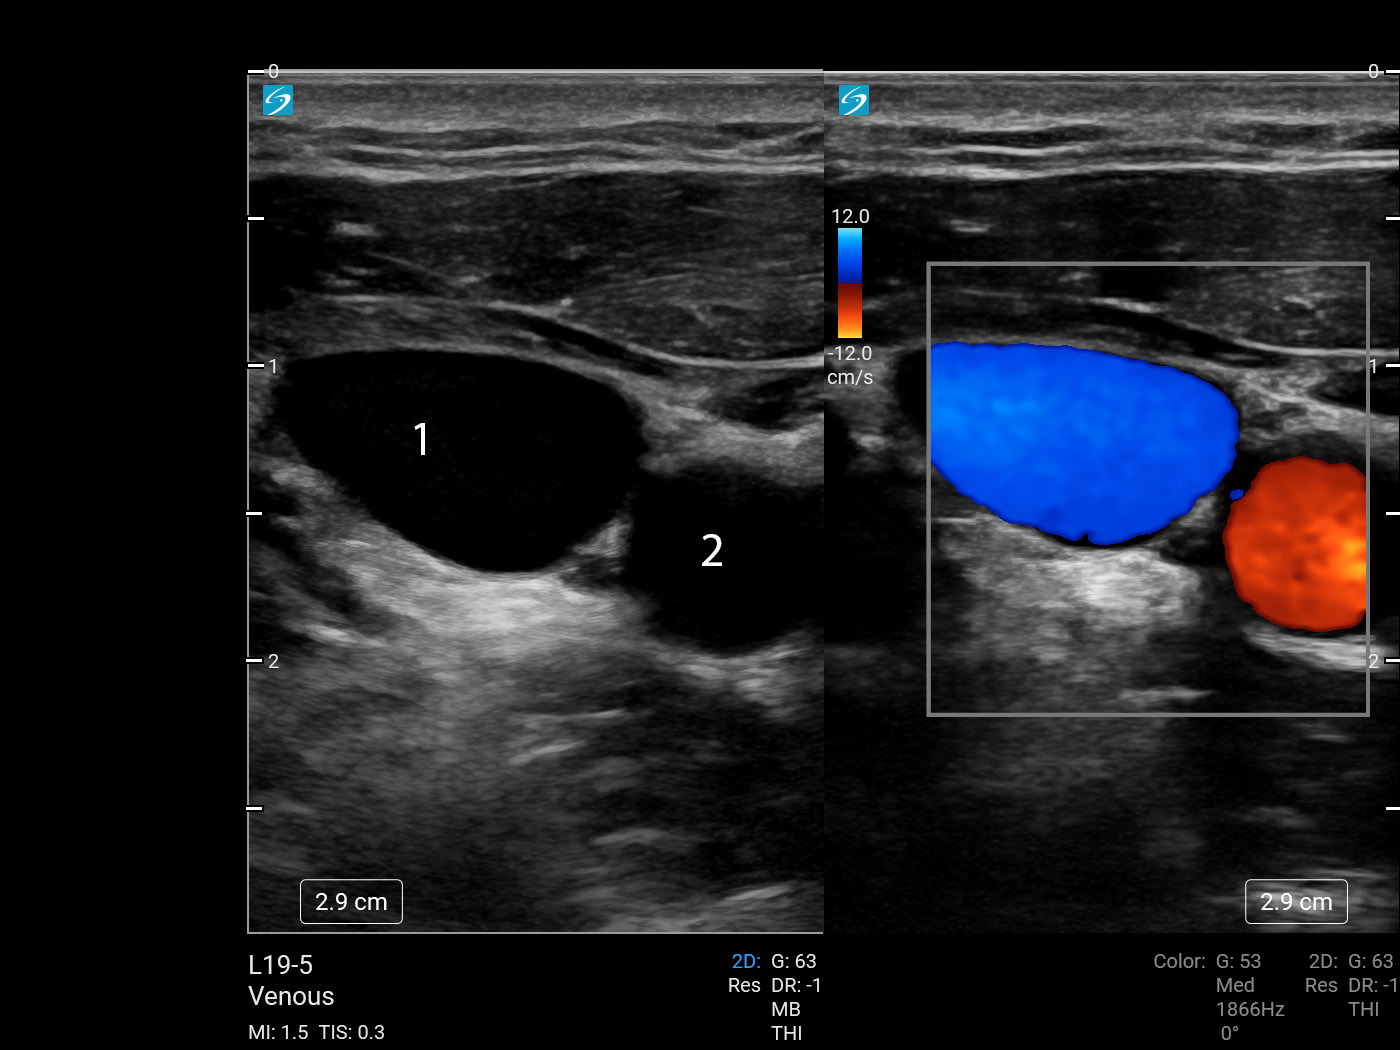

Vascular Internal Jugular Vein (IJV) 2 (Sonosite PX L19-5) Image

1. Internal Jugular Vein (IJV)

2. Common Carotid Artery (CCA)